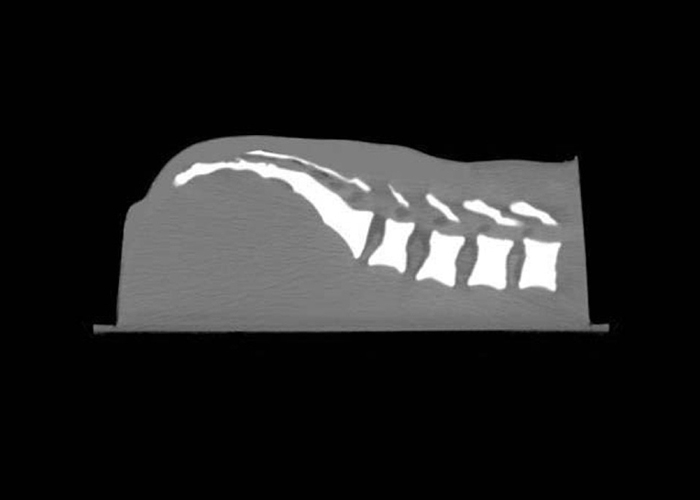

Lumbar Training Phantom

- Realistic needle resistance of each tissue to allow the trainee to “feel” the injection site

- Train many spinal procedures including sacroiliac joint injection, lumbar and caudal epidurals, diskography, block nerves, and facet blocks

- Can be imaged under Fluoroscopy, CT, MR, and ultrasound

Dimensions |

38 cm x 25 cm x 18 cm |

Weight |

19 lbs. (7.1 kg) |

Materials |

Epoxy Resin (bony spinal structures) Urethane (soft spinal structures) Zerdine® (soft tissue) |